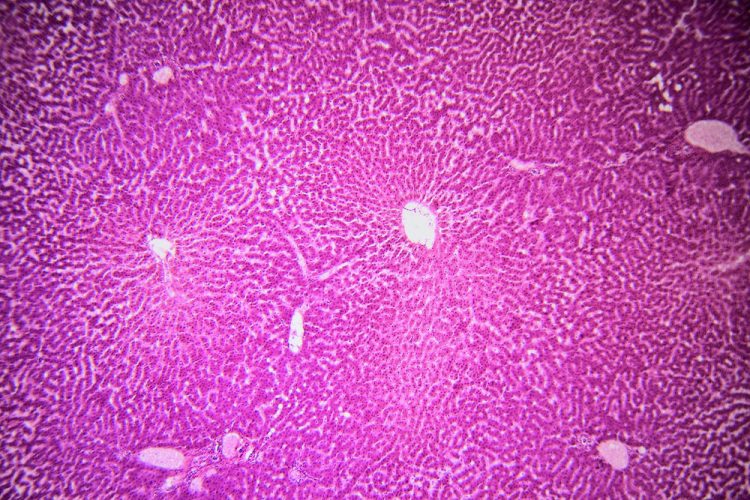

Scientists have developed a 3D liver model, known as the periportal assembloid. This model replicates the liver’s complex structure and bile transport system, enabling more precise study of disease progression.